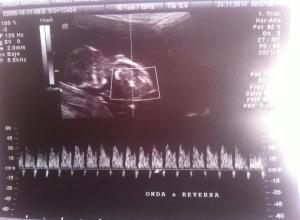

El dia de ayer, tuvimos otra revisión, después de un ultrasonido, nos dieron la noticia el bebe tiene alguno de los 3 síndromes que mencionaremos, Síndrome de Edwards, Síndrome de Patau, o Síndrome Down, aparte de eso, tiene una pequeña complicación en su corazón, algo en su “Ductus Venoso, con onda “A” reversa”, (Cada latido que da su corazon, la sangre que corre por sus venas, tiene un pequeño regreso).